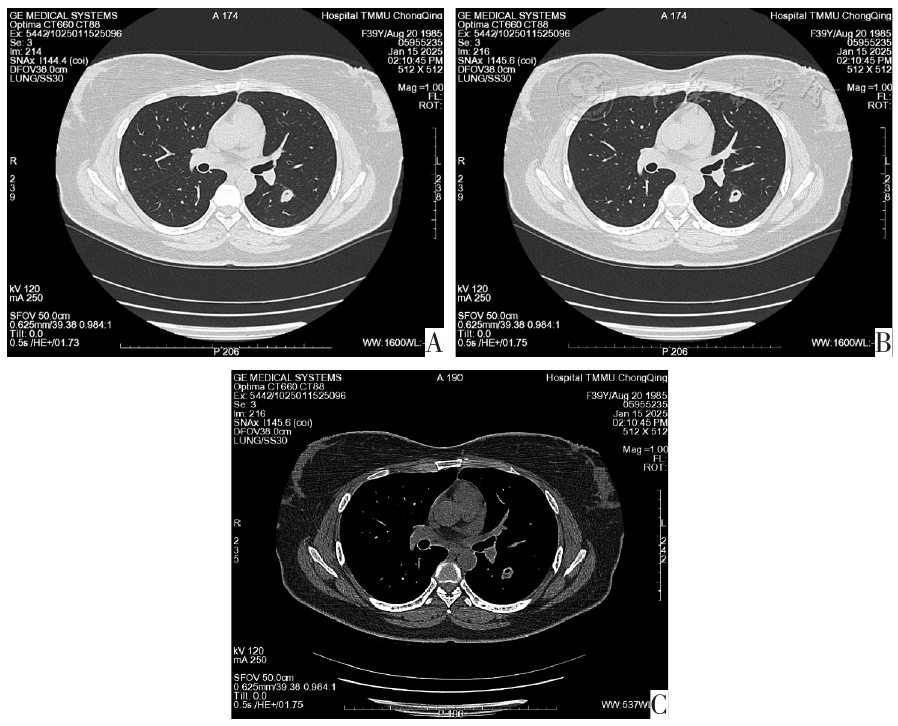

图1 2025-1-15肺部CT扫描图像。图A为左肺下叶背段实性结节,直径为18 mm×13 mm,结节内见空洞;图B为左肺下叶背段实性结节周围见浅淡模糊影及小结节影;图C为纵膈窗未见肿大淋巴结